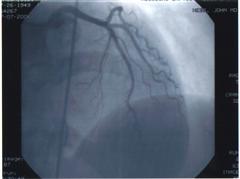

Heart 1 Heart 2